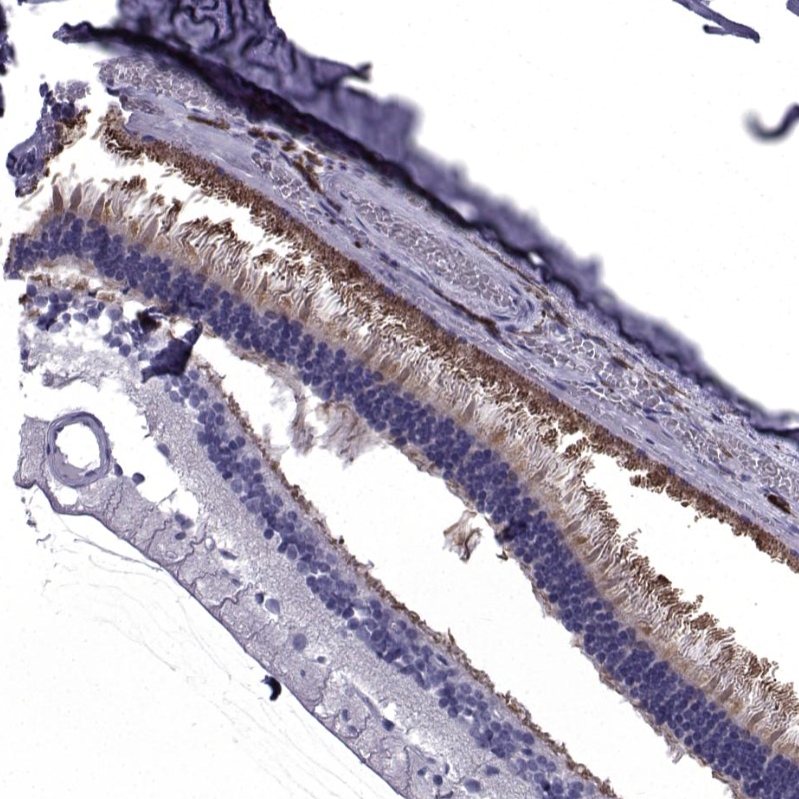

Immunohistochemical staining of human eye, retina shows strong cytoplasmic positivity in photoreceptor cells.